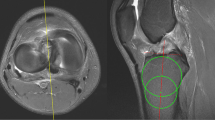

The mean medial PTS for the full sample was 8.8 ± 3.3° (range 1–17°). There was no statistically significant difference in medial PTS between the different types of injury mechanisms observed (non-significant [n.s.]): sports-related (8.8 ± 3.0°), traffic-related (8.9 ± 3.4°), non-sports and non-traffic-related traumatic impact to anterior proximal tibia (9.1 ± 3.0°), and hyperextension (7.3 ± 3.7°). In addition, there was no statistically significant difference in medial PTS between patients undergoing isolated and combined PCL-R (8.4 ± 3.4° vs. 9.0 ± 3.2°, n.s.; Fig. 2).

Isolated vs. combined PCL-R. A Patient-reported outcome scores (PROs). Indicators (triangle, rhombus) represent mean values. Error bars represent standard deviation. B Medial posterior tibial slope (PTS). ADL activities of daily living, IKDC-SKF International knee documentation committee subjective knee form, KOOS knee injury and osteoarthritis outcome score, PCL-R posterior cruciate ligament reconstruction, Sport/Rec sport and recreation function, QOL knee-related quality of life; No statistically significant difference was found between isolated and combined PCL-R with respect to PROs and medial PTS (n.s.)

At a mean follow-up of 5.7 ± 3.3 years (range 2.0–12.4 years), PROs were available for 57 (72%) patients. A detailed summary of the PROs data is shown in Table 3. There was no statistically significant difference in PROs between patients undergoing isolated and combined PCL-R (n.s.; Fig. 2) and between patients with and without PCL graft failure (n.s., Table 2). In addition, there were no statistically significant correlations between medial PTS and any of the PROs (Table 4, n.s.).